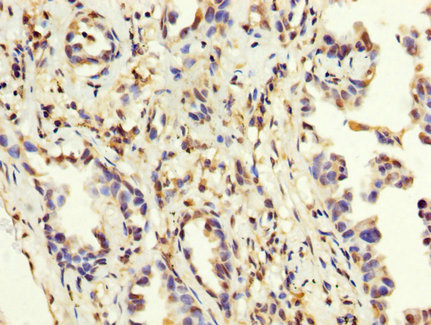

IHC image of CSB-PA013329LA01HU diluted at 1:200 and staining in paraffin-embedded human melanoma performed on a Leica BondTM system. After dewaxing and hydration, antigen retrieval was mediated by high pressure in a citrate buffer (pH 6.0). Section was blocked with 10% normal goat serum 30min at RT. Then primary antibody (1% BSA) was incubated at 4°C overnight. The primary is detected by a biotinylated secondary antibody and visualized using an HRP conjugated SP system.